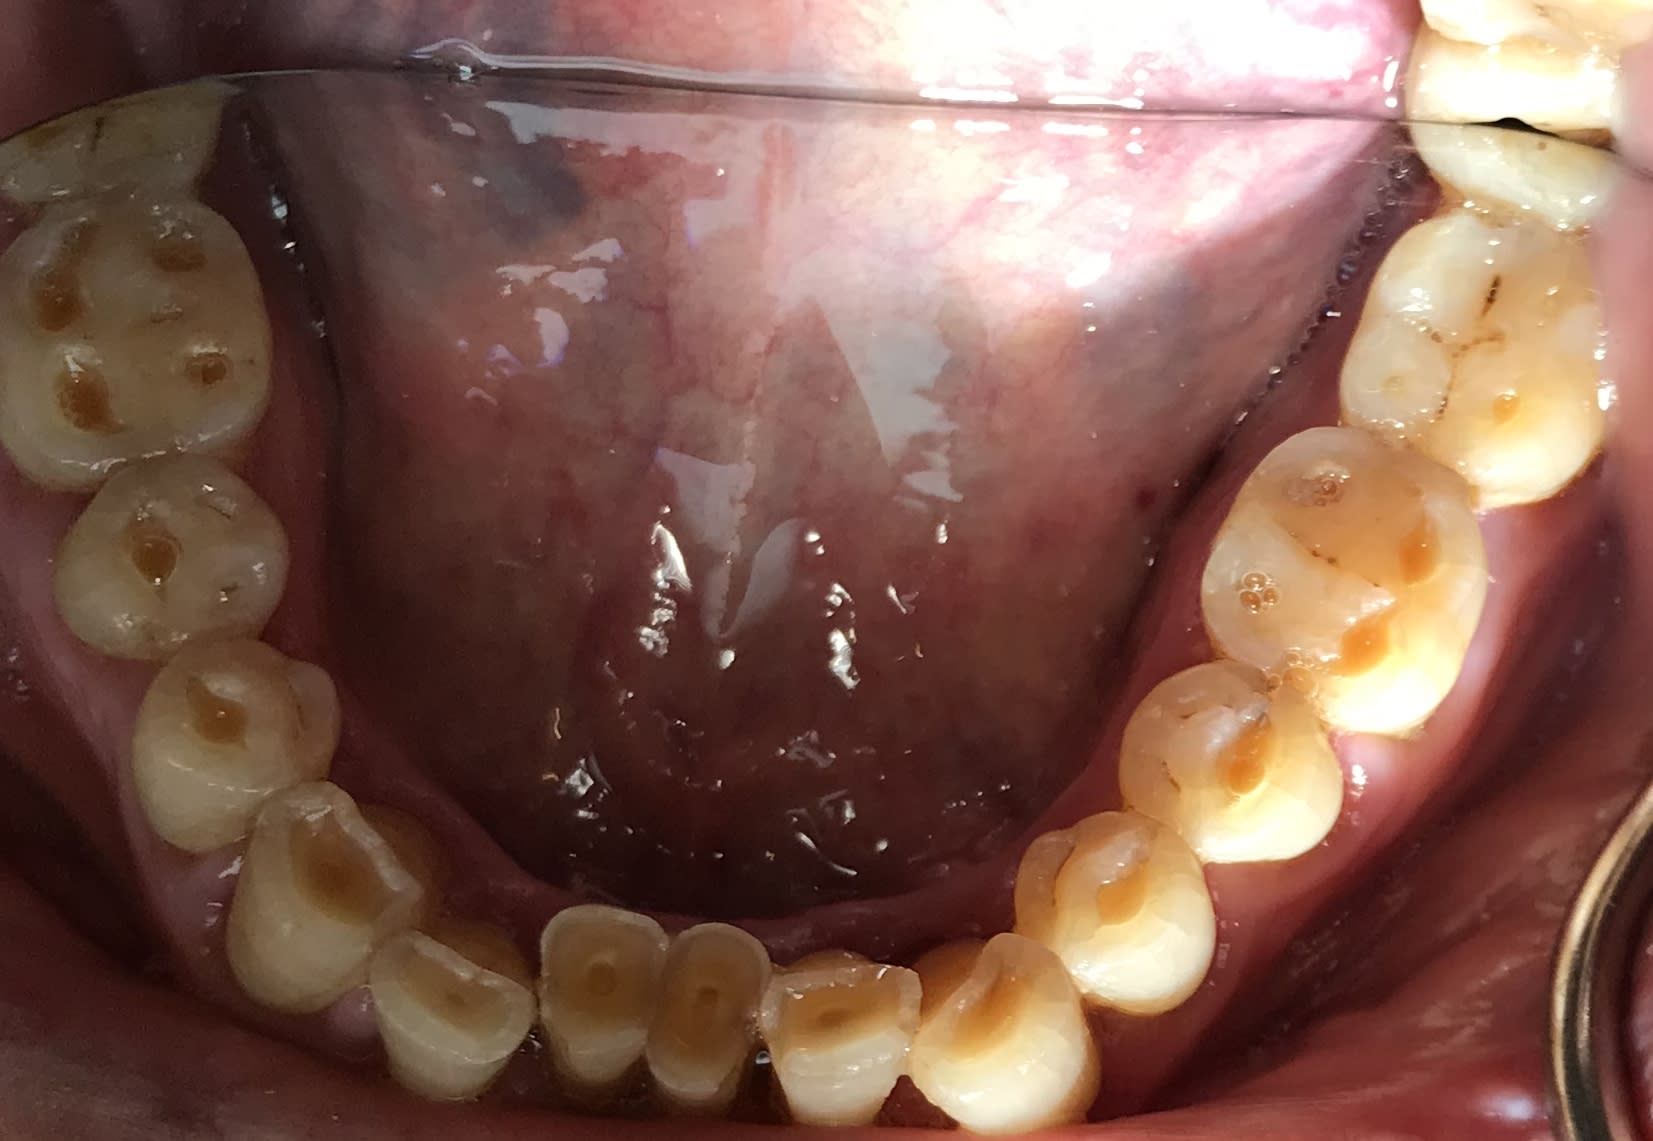

Usure de dents sur une vieille branche de 80 ans

672aae55 c287 4cbf bc72 24a92f326d67 bzqyov - Eugenol

Cb933ae5 b44d 4e23 a1d0 0013af93a7a4 p5qelm - Eugenol

Screenshot 20190204 160354 2 ookelm - Eugenol

11/07/2019 à 11h42

Il y aurait des enseignements à en tirer.

Qu'il est urgent de faire un truc tout simple.

Oui c'est pas top, MAIS cela limite l'abrasion chimico- mécanique. Sinon tu vas avoir une accélération de l'usure de la dentine, normal hein... Puis des factures de coques d'email, voir des atteintes pulpaires.

C'est pas top, ça tient plutôt bien et ça limite les dégâts.

Que sur les grosses érosions.